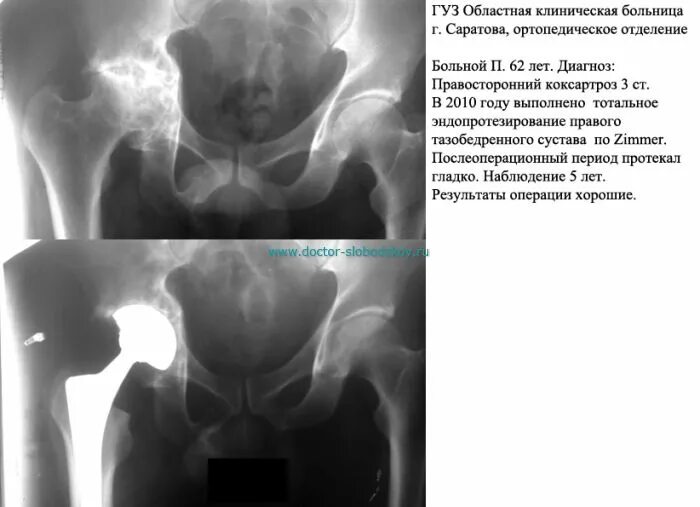

Коксартроз тазобедренного сустава код